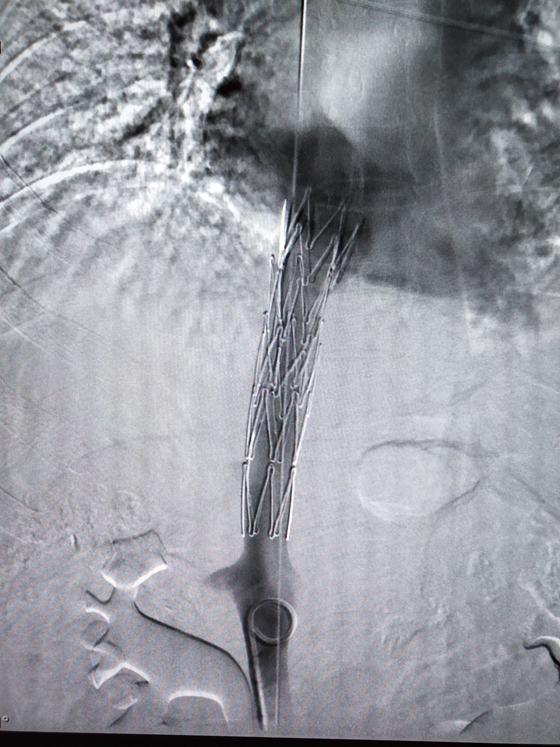

家住湖南澧县的47岁严大叔两天前突然出现胸背部撕裂样剧烈疼痛,来我院急诊就诊,行全主动脉CT显示:主动脉弓(锁骨下动脉分叉以远)至左髂外动脉夹层。明确病情后,由于病情严重,大动脉...